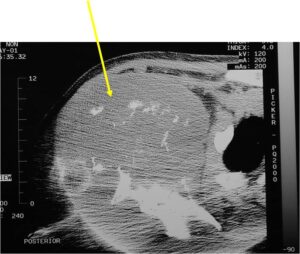

- Second more aggressive area with bone destruction, lysis of calcification, soft tissue mass

- Cortical permeation and a soft tissue mass in 70% of cases

- Or extraosseous soft tissue mass

Characteristically abrupt transition between chondroid tumor and dedifferentiated, lytic component